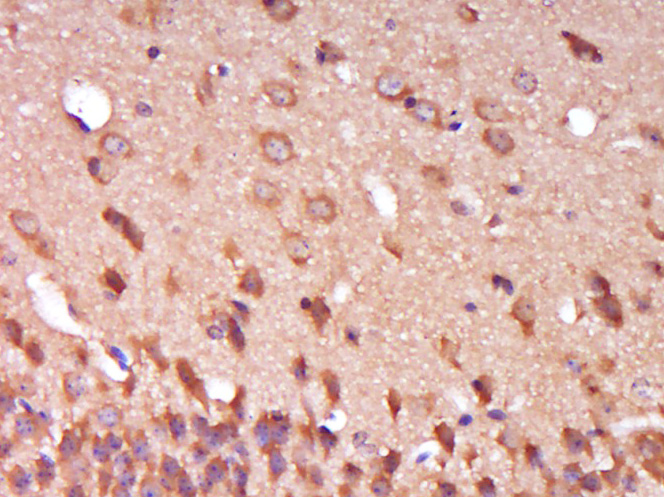

Paraformaldehyde-fixed, paraffin embedded (Mouse brain); Antigen retrieval by boiling in sodium citrate buffer (pH6.0) for 15min; Block endogenous peroxidase by 3% hydrogen peroxide for 20 minutes; Blocking buffer (normal goat serum) at 37°C for 30min; Antibody incubation with (SPG11) Polyclonal Antibody, Unconjugated (bs-17656R) at 1:400 overnight at 4°C, followed by operating according to SP Kit(Rabbit) (sp-0023) instructionsand DAB staining.